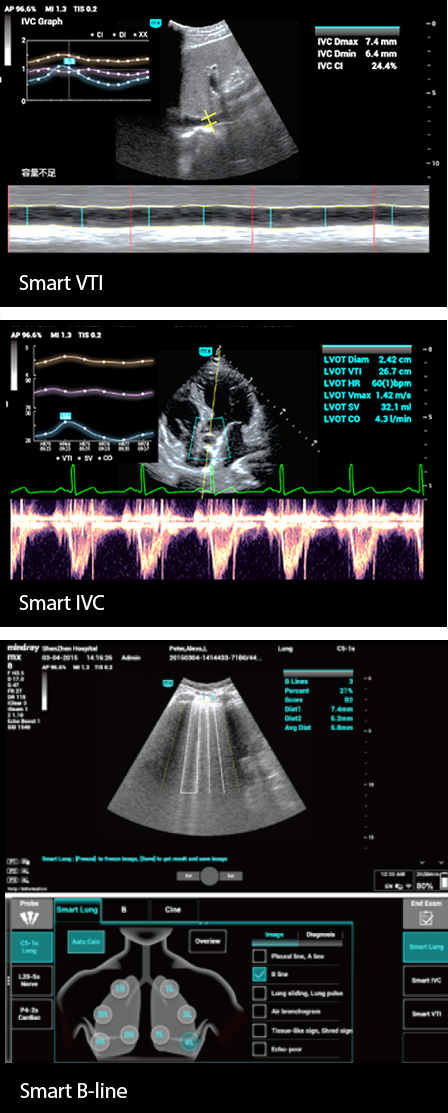

Yo?un bak?m ĂŒnitesindeki hastalarda ?o?unlukla kardiyopulmoner, hepatik ve renal organ yetmezli?i veya yetersizli?i vard?r, hayati belirtiler her an de?i?ebilir ve kritik hastalar?n yakla??k %90'?nda vĂŒcut s?v?lar? h?zla de?i?ir. Yo?un bak?m ĂŒnitesinde vĂŒcut s?v?lar?ndaki de?i?ikliklere yans?yan, yayg?n g?rĂŒlen anormallikler, gastrointestinal kanama, ciddi endokrin ve metabolik bozukluklar, su-elektrolit ve asit-baz dengesindeki bozukluklar, karaci?er ve b?brek fonksiyon bozuklu?udur.

Bu nedenle, hastalarda yak?n s?v? izlemesi ve do?ru hacim y?netimi yap?lmas? bĂŒyĂŒk ?nem ta??r. Ancak ultrason, hastalar?n kardiyopulmoner fonksiyonlar?n?n ve hemodinamiklerinin dinamik olarak de?erlendirilmesinde daha sezgisel olma avantaj?na sahiptir ve yo?un bak?m ĂŒnitesindeki sa?l?k mesle?i mensuplar?n?n, zaman?nda tedavi kararlar? almas?na ve tedavinin etkilerini ger?ek zamanl? olarak g?zlemlemesine yard?mc? olabilir.

Bu nedenle, hastalarda yak?n s?v? izlemesi ve do?ru hacim y?netimi yap?lmas? bĂŒyĂŒk ?nem ta??r. Ancak ultrason, hastalar?n kardiyopulmoner fonksiyonlar?n?n ve hemodinamiklerinin dinamik olarak de?erlendirilmesinde daha sezgisel olma avantaj?na sahiptir ve yo?un bak?m ĂŒnitesindeki sa?l?k mesle?i mensuplar?n?n, zaman?nda tedavi kararlar? almas?na ve tedavinin etkilerini ger?ek zamanl? olarak g?zlemlemesine yard?mc? olabilir.